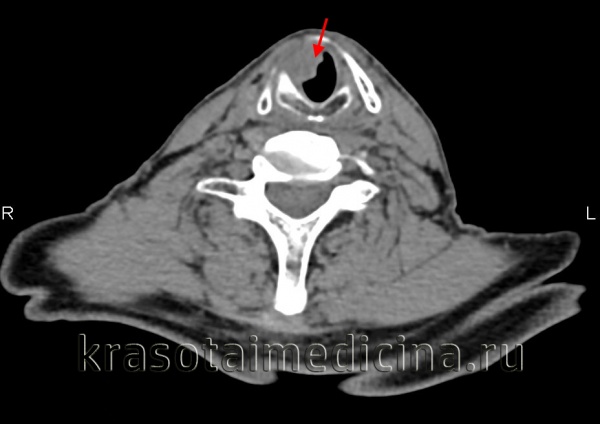

КТ шеи. Рак связки гортани с сужением ее просвета.